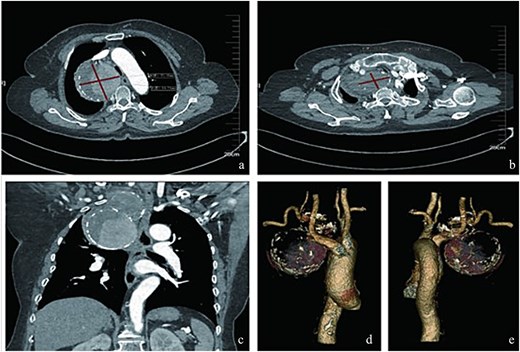

A 75-year-old female patient was admitted because of intermittent chest pain and dyspnea for 2 weeks. A thoracic aorta computed tomography angiography (CTA) demonstrated a large right proximal SAA with partial thrombosis, and the adjacent trachea, esophagus, and blood vessels were obviously compressed and displaced (Fig. 1). Physical examination revealed wheezing and phlegm sounds in the chest, and no obvious pulsatile mass was found in the right supraclavicular fossa.

Radiologic characteristics of the SAA. (a) Axial CTA demonstrates a bipartite aneurysm morphology with superior–inferior compartmentalization. The inferior spherical component measures 70.05 mm (long axis) × 69.73 mm (short axis), exhibiting regular contour and homogeneous attenuation. (b) The superior ellipsoid component displays dimensions of 51.81 mm (long axis) × 35.59 mm (short axis), with peripheral thrombus formation. (c) Coronal reformation reveals the characteristic gourd-shaped configuration and intraluminal thrombus burden. (d and e) Volume-rendered reconstructions delineate circumferential calcifications along the aneurysm wall, particularly prominent at the inflow/outflow transitional zone.